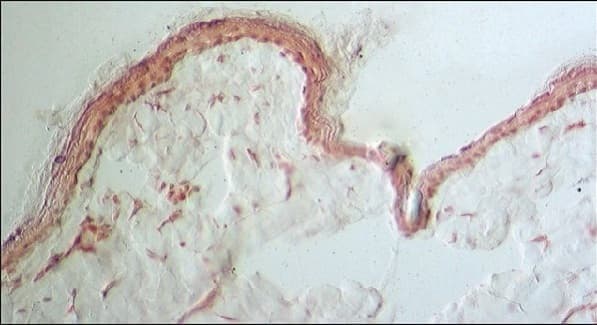

Anti-Collagen III antibody [FH-7A] ab6310 is a mouse monoclonal antibody that is used in Collagen III western blotting, IHC and immunofluorescence. Suitable for human and rat samples.

Applications Dot, ELISA, ICC/IF, IHC-Fr, IHC-P, WB